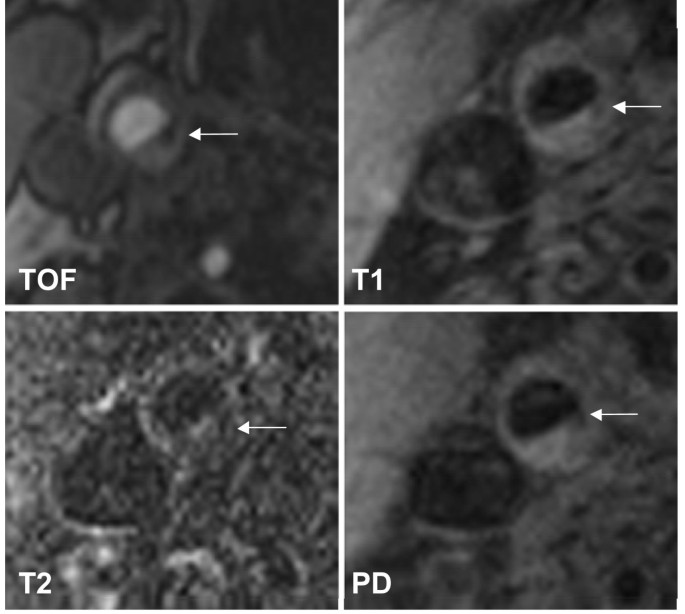

All subjects were imaged with a 1.5-T scanner (Magnetom Symphony Quantum Gradient; Siemens Medical System; Germany) with bilateral phased-array surface coils (PACC-SS15; Machnet B.V., Netherlands). According to our previously published protocol, four contrast-weighted images were obtained as follows: 3-dimensional time-of-flight MR angiography (3D TOF), T1-weighted (T1w), T2-weighted (T2w), and proton-density-weighted (PDW) studies of both carotid arteries. The MRI scan was centered on the carotid bifurcation on the side of the stenosis to assure proper matching between the contrast-weighted imaging series of each patient. The imaging sequences were as follows: 3D TOF: field of view (FOV) 200 mm/75.0%; repetition time (TR) 43 ms; time to echo (TE) 7.15 ms, number of excitations (NEX) 2. T1w: FOV 160 mm/100%; TR 700 ms; TE 14 ms; NEX 2. T2w: FOV 160 mm/100%; TR 700 ms; TE 100 ms; NEX 2. PDW: FOV 160 mm/100%; TR 700 ms; TE 10 ms; NEX 2. Slice thickness was 1 mm for the 3D TOF and 2 mm for the T1w, T2w, and PDW images. The longitudinal coverage of each carotid artery was 72 mm (72 slices) for the 3D TOF and 24 mm (12 slices) for T1w, T2w, and PDW images.

Before evaluating the MRI scans, an image quality rating (4-point scale; 1 = best, 4 = worst) was assigned to all MR images for each contrast-weighted-image. Image quality = 4 in one of the contrast weightings led to exclusion of the evaluation procedure. For each patient, a data set of 108 contrast-weighted MR images (72 slices for the 3D TOF and 12 slices for T1w, T2w, and PDW) of the carotid arteries was obtained. The images were evaluated by two experienced reviewers. A consensus opinion was reached for each image analysis. The reviewers were blinded to the patient's clinical history at the time of image analysis. To determine the lesion type in accordance with the modified AHA criteria, the carotid atherosclerotic plaque in the 108 images of each patient was identified and 6 sequentially acquired slices of each contrast weighting in the region of the minimum lumen area were selected for evaluation. The carotid atherosclerotic plaque in these selected slides was ascribed to one of the six classification types according to the following modified AHA criteria: Type I-II shows near-normal wall thickness without calcification. Type III represents diffuse intimal thickening or small eccentric plaque without calcification. Type IV-V is characterized by a lipid or necrotic core surrounded by fibrous tissue with possible calcification. Type VI shows a complex plaque with possible surface defect, hemorrhage or thrombus. Type VII represents a calcified lesion. Type VIII is characterized by a fibrotic plaque without a lipid core and with possible small calcifications.

We recruited 31 subjects with asymptomatic carotid artery stenosis. Twenty-three plaques were classified as stable according to the modified AHA-classification (types III, VII, and VIII) and 8 were classified as unstable (types IV-V and VI). Figure 1 shows a representative case of lesion type IV-V, Figure 2 shows a representative case of lesion type VIII. Subjects with stable plaques did not differ significantly from the subjects with unstable plaques concerning age, sex, and cardiovascular risk factors (Table 1).